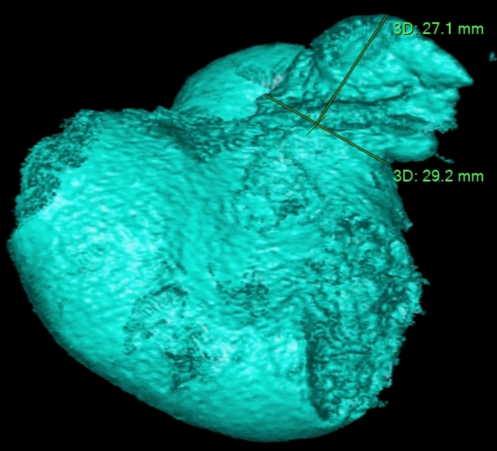

术前左心房CTA- 3D评估:左心耳开口区29.2mm,深度 27.1mm。